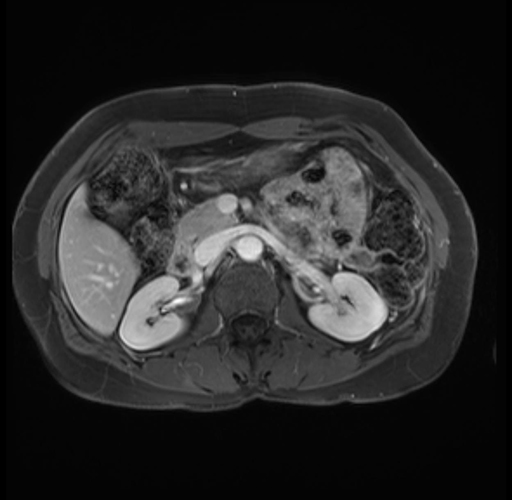

Imaging Analysis

Look through the patient's CT scan to identify any areas of concern for the necessary procedure.

Based on your CT findings, which issue(s) are present and would give reason for "planned slowing down moment(s)" in this case?

Considering a standard distal pancreatectomy procedure, what step(s) of the operation would you do differently in this case?